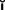

Successful tooth preparation and subsequent restoration depend on simultaneous consideration of all these factors. Improvement in one area often adversely affects another area, and striving for perfection in one may lead to failure in another. For example, in the fabrication of a metal-ceramic crown (see Chapter 24), sufficient thickness of porcelain is necessary for a lifelike appearance. However, if too much tooth structure is removed to accommodate a greater thickness of porcelain for esthetic reasons, the pulpal tissue may be traumatized (biologic consideration) and the tooth unduly weakened (mechanical consideration). In-depth knowledge and an understanding of the various criteria are prerequisite to the development of satisfactory tooth preparation skills. Predictable accomplishment of optimum tooth preparation (Fig. 7-1) often includes finding the best combination of compromises among the applicable biologic, mechanical, and esthetic considerations.